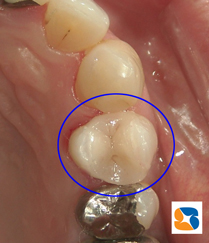

オールセラミックの詰め物 オールセラミックの白い詰め物

11月末。30代の女性。主訴は「犬歯の横の詰め物が取れた」でした。患者様にはセラミックの詰め物の強度、無変色、虫歯になりにくい長所をご理解して頂いたうえで、白いセラミックの詰め物を選択されました。

参考)治療回数は2回。総額¥45,000円。